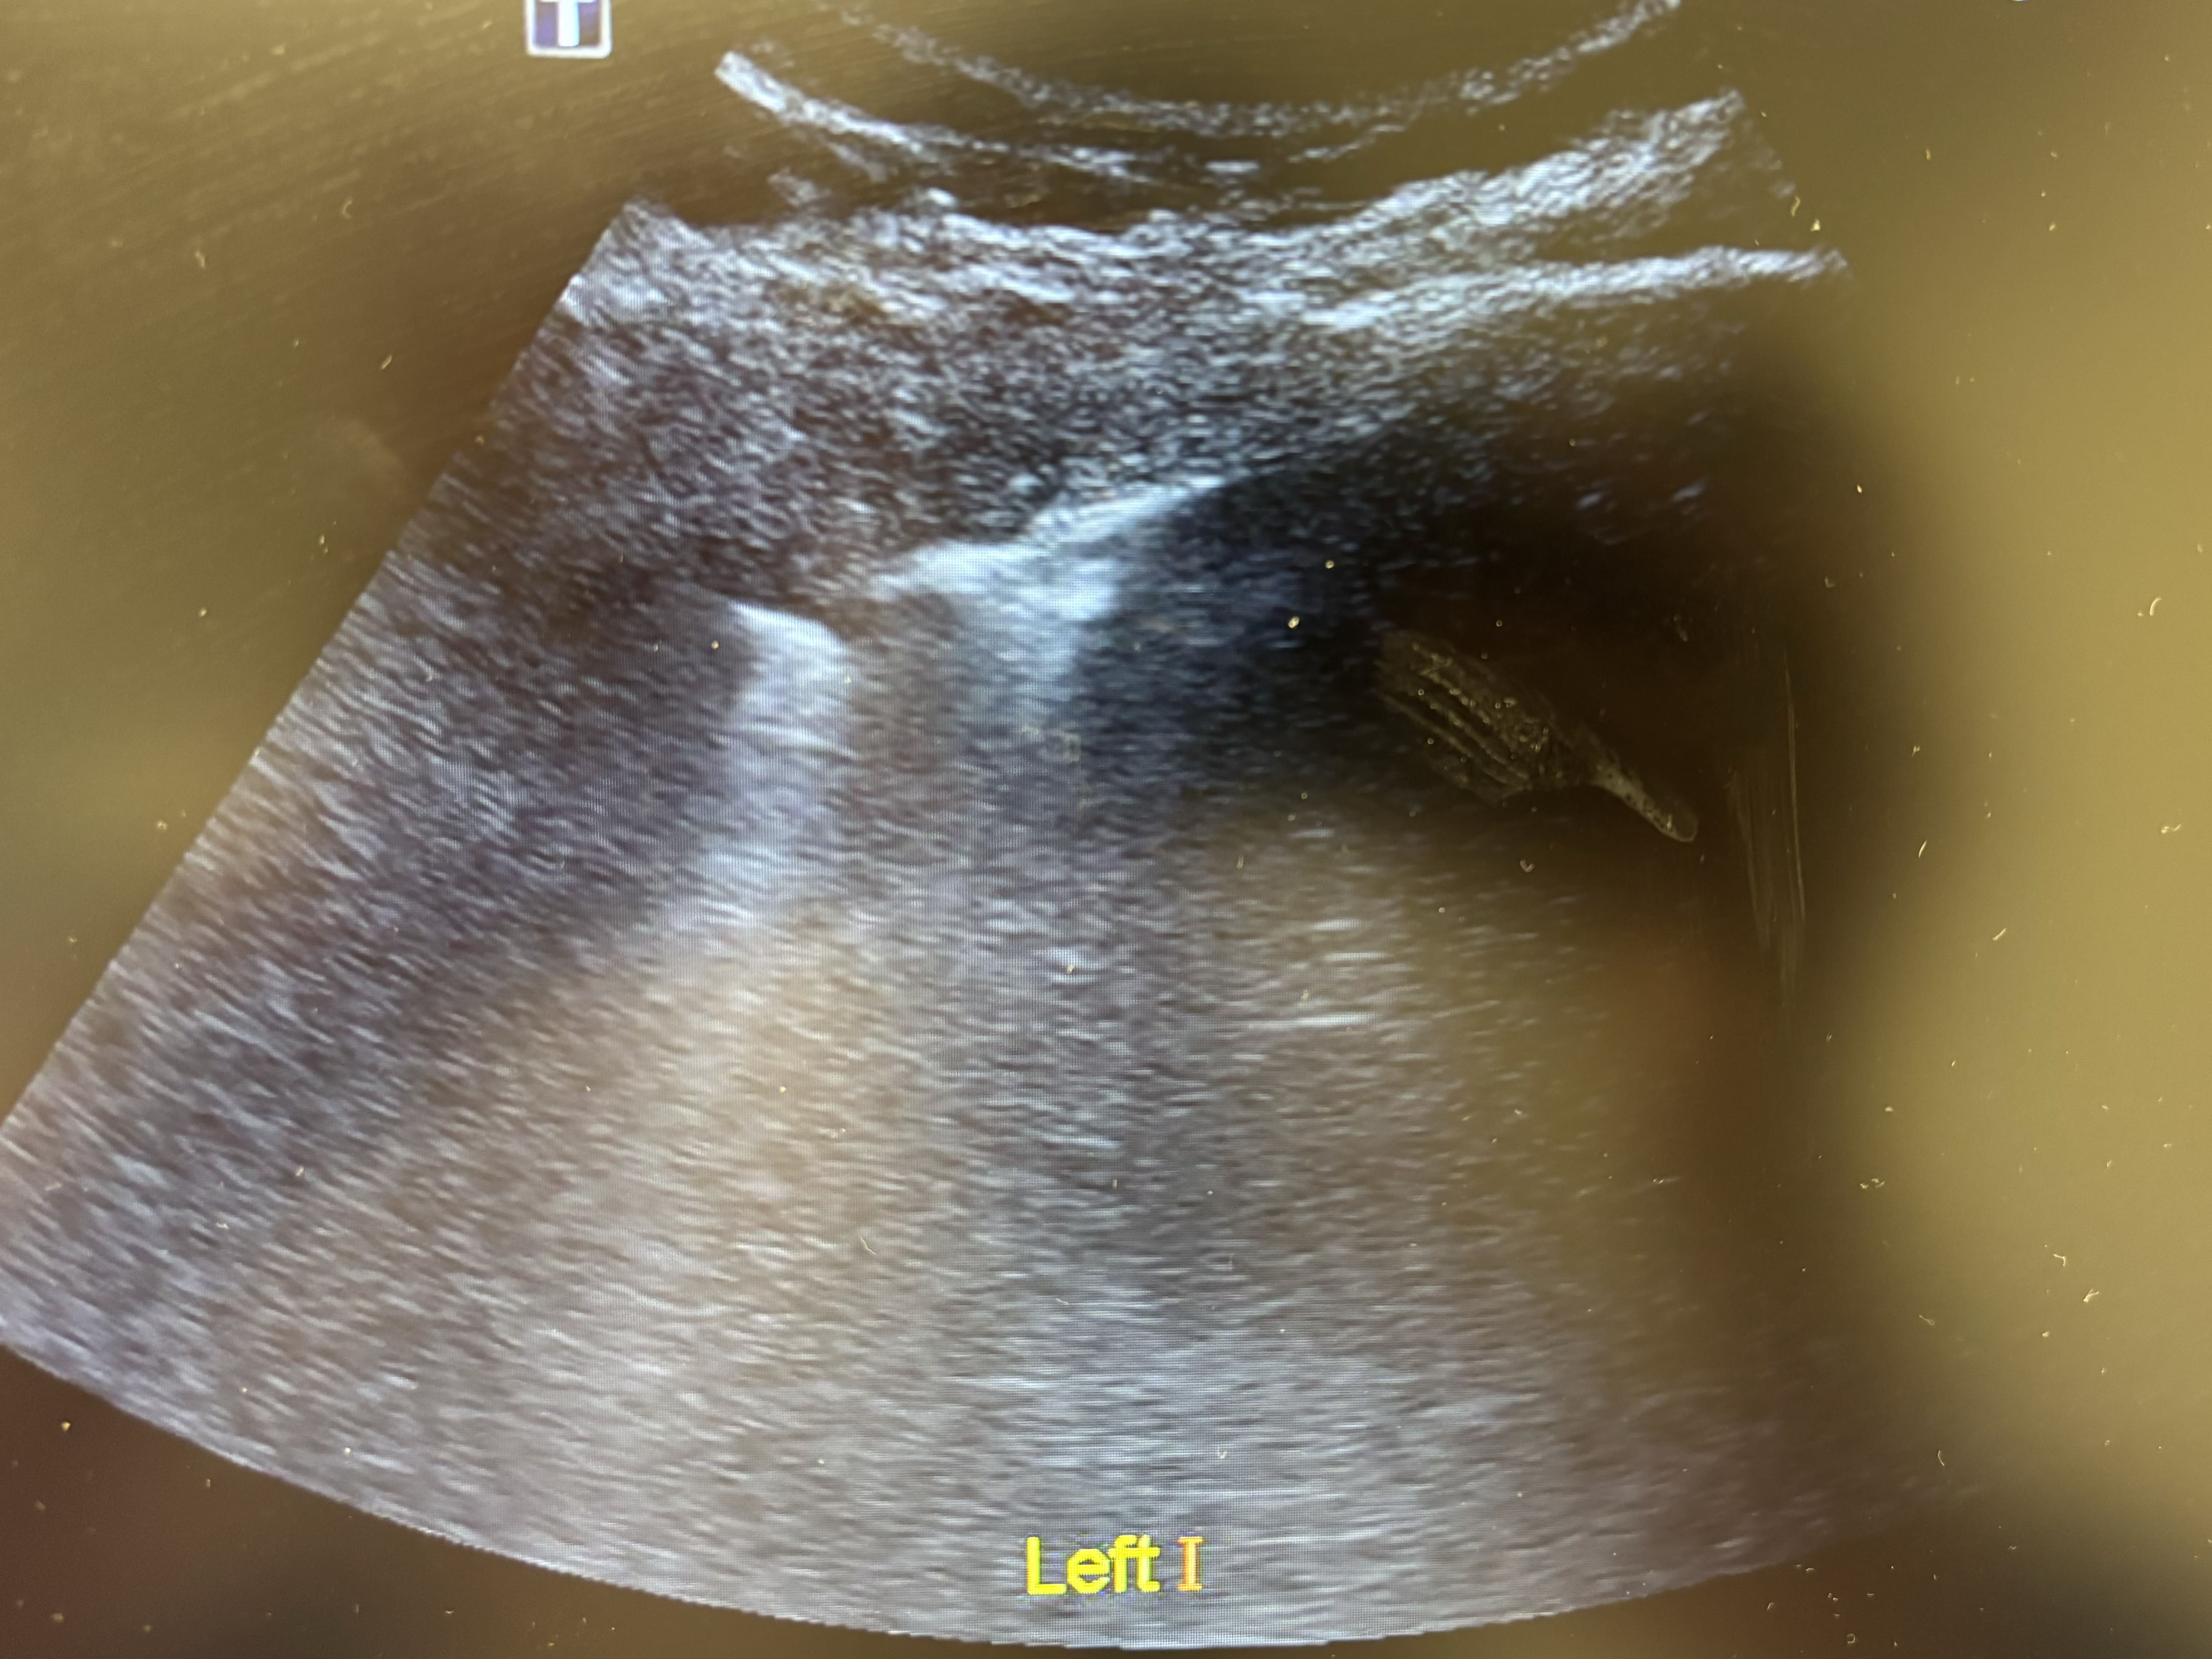

Antes de solicitar otras pruebas complementarias, se decide realizar ecografía clínica pulmonar. Se detecta un patrón intersticial focal en base izquierda, con condensación basal, mínimo derrame pleural y líneas B periféricas. Deslizamiento pleural conservado bilateral.

Como curiosidad, las neumonías suelen presentarse como área hiperecoicas o con sombras acústicas en casos más graves.